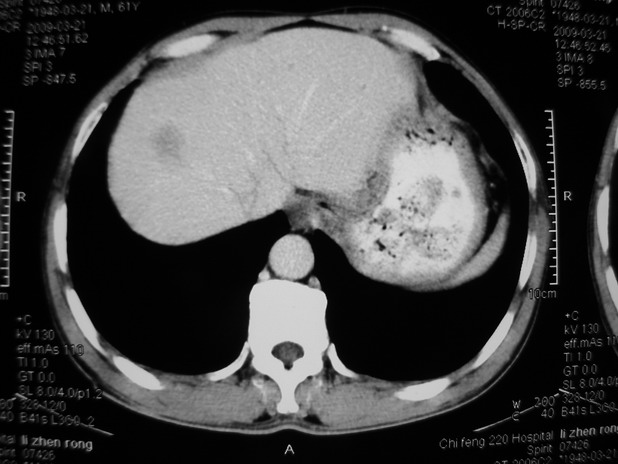

以下是引用余辉在2009-3-21 21:36:00的发言:[br]图像太乱了,建议楼主直接将强化数据按顺序列出来,病灶位置较表浅薄,有肝炎病史,灶内实性成分有显著强化,动脉期约60hu,考虑肝癌可能性大,进一步检查。